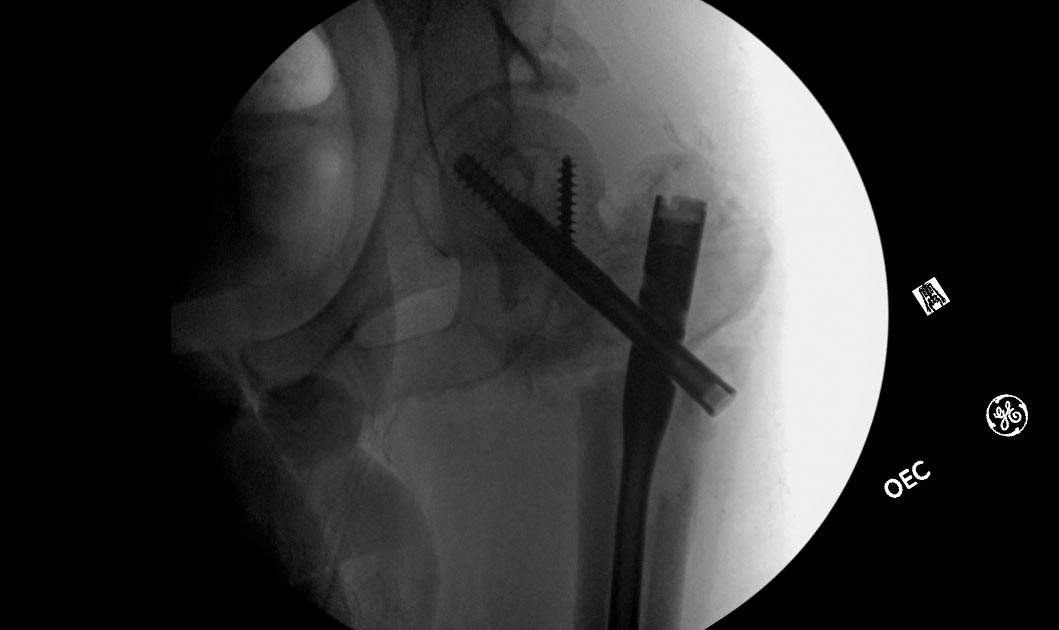

Насчет ревизионного штифтования - вот пример, вчера сделали.

Имя     : 1.jpg

Тип     : image/jpeg

Размер  : 68892 байтов

Url     : http://weborto.net:8080/pipermail/ortho/attachments/20130531/0a9354ad/attachment-0004.jpg